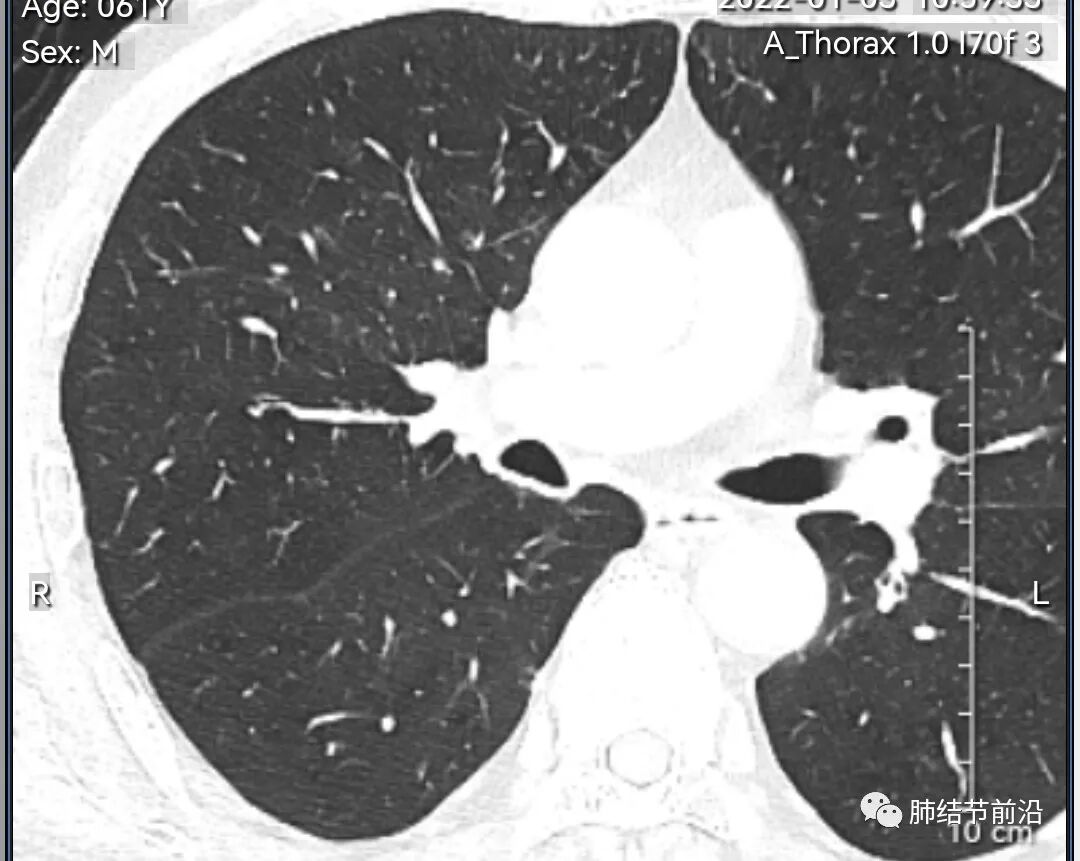

男性,67岁,重度吸烟史。CT发现右下肺囊腔。来看一下这个CT的特点:

该囊腔形态非常有特点,和常见的圆形肺大泡有很大的区别。

1.囊腔中央实性成分,周围有磨玻璃影。

2.囊腔中央有血管。

3.囊腔外周有分叶形态。

4.囊腔有胸膜牵拉。

出现这几种形态,CT可以确认恶性的腺癌。这个囊腔形成的机制,为肿瘤实性成分堵塞细支气管形成活瓣,肺泡内压力增高破裂行成,因此肺内血管成分保留。由于肺泡压力增高,而呈分叶状。另外,也有肿瘤的胸膜牵拉这一特点。

囊腔周围磨玻璃+囊腔中央血管为特征性表现。如果持续存在,几乎可以100%确认为早期肺腺癌。

建议患者手术切除,术后病理为浸润性腺癌,腺泡型,部分为实体型。IA1期,术后不用治疗。